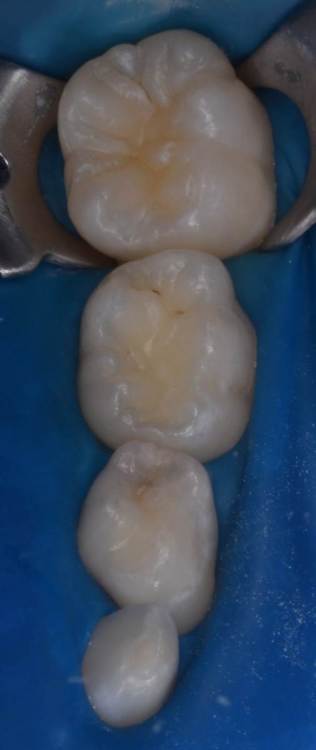

CRAZYDUCK Опубликовано 29 июня, 2022 Автор Поделиться Опубликовано 29 июня, 2022 Герметизация тоже в изоляции . по случаю - герметизация 3.6 лечение кариеса 74 ,75 . 3 1 Ссылка на комментарий